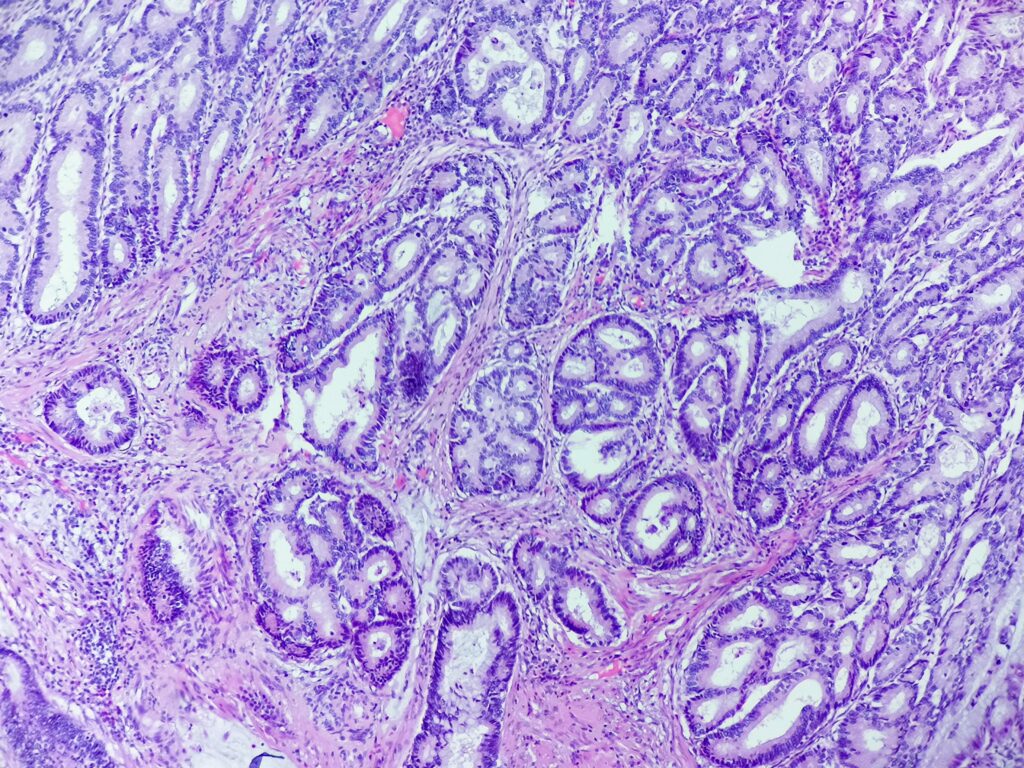

Obrazy mikroskopowe: